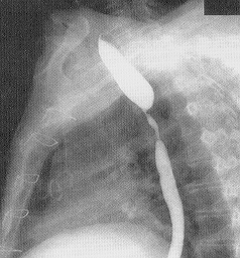

Diaqnostikası

Dəqiqləşdirmə

Diaqnozun dəiqiləşdirilməsi üçün kontrastlı Rentgenoloji müayinələr, KT və çox ehtiyatla endoskopiya edilir.

- Kontrastlı Rh-qrafiya - diaqnozu dəqiqləşdirən müayinədir.

- Rentgenoqrafik divertikul görünməsi

Xəstəliyin dəqiqləşdirilməsi üçün kontrastlı Rentgenoloji müayinə, KT və çox ehtiyatla endskopiya edilməlidir.

- Kontrastlı rentgenoqrafiya - dəqiqləşdirici müayinə üsuludur.

Diaqnostik meyarlar:

- Kontrastlı Rentgenoloji müayinədə və ya KT-də divertikul görünməsi

- Kontrastlı müayinələrdə (Rh-qrafiya, KT) divertikul görünməsi

Görüntlüləmə əlamətləri hansılardır?

Kontrast məhlulunn divertikul nahiyəsində toplanması

Kontrast məhlulun divertikul nahiyəsində toplanması

Görüntlüləmə əlamətləri hansıdır?